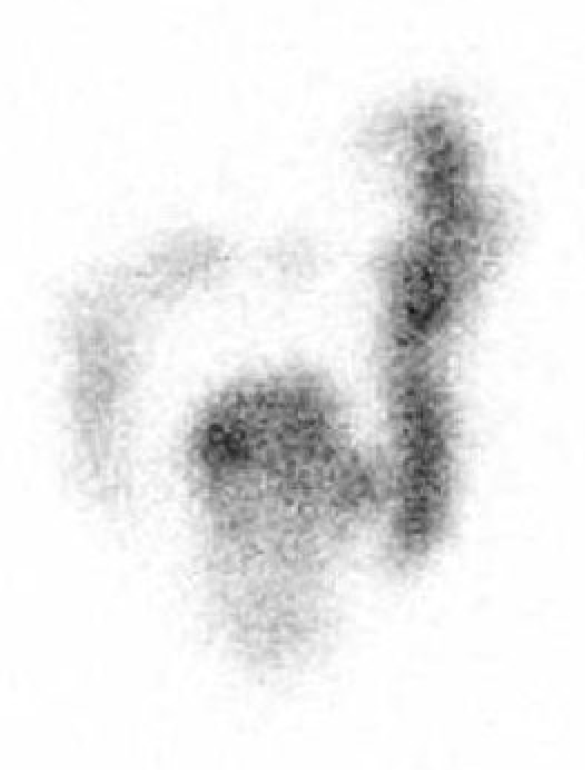

In men group of patients there was a noticeable slowing down of colonic transit in the descending colon and rectosigmoidal segment of Figure 3 and Figure 4.

Figure 3. Static scintigram in anterior projection, 48 hours after administration of radiofarmaceutical. Male 37 years old, with constipation symptomatology. Qualitatively retention of radiopharmaceutical was observed predominantly in descending and rectosigmoid part of the colon. GC value was 2,2.